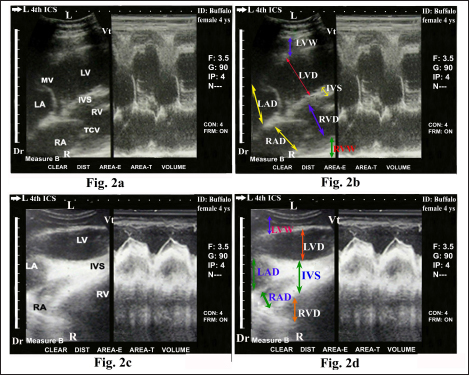

Ultrasonography of the normal heart in the healthy buffaloes was imaged from the left fourth ICS in midway between the elbow point and shoulder point as the transducer directed dorsally and slightly cranially toward the left fifth ICS showed the four chamber view either in diastole (Fig. 2a and b) or systole status (Fig 2c and d); right atrium (RA), right ventricle (RV), tricuspid valve (TCV), left atrium (LA), left ventricle (LV), mitral valve (MV), and interventricular septum (IVS).

Fig. 2. Echocardiogram of caudal long axis view in adult healthy female non-pregnant (4-year-old) buffalo (left side) during diastole (a and b) and systole (c and d) using a 3.5 MHz sector 2-D-gray scale transducer (B-mode and M-mode). It was imaged from the left fourth ICS in midway between the elbow point and shoulder point as the transducer directed dorsally and slightly cranial toward the left fifth ICS. It showed a normal heart with regular, strong contractions and clear margins. The four chambers view was imaged where it included the RA, RV, TCV, IVS, LA, LV, LV, MV. Echocardiographic dimensions, either in diastole or in systole, were also visualized, including right ventricular diameter (RVD), right ventricular wall thickness (RVW), right atrial diameter (RAD), right atrial wall thickness (RAW), IVS, left ventricular diameter (LVD), left ventricular wall thickness (LVW), left atrial diameter (LAD) and left atrial wall thickness (LAW). Dr; Dorsal. Vt; Ventral. R; Right. L; Left.

Buffalo echocardiography was a practical method that needed physical strength because buffaloes resisted the positioning and rotation of the transducer to produce uniform images (Torad et al., 2017; Chavez et al., 2021). The current study showed that the heart in healthy buffaloes was normally imaged ultrasonographically using 2-D B-mode and M-mode gray-scale from the left fourth ICS in the midway between shoulder point and elbow point as the transducer directed dorsally and slightly cranially toward the left fifth ICS where it showed the four-chamber view (RA, RV, LA, LV, TCV, MV, and IVS). These results coincided with the results reported by Braun et al. (2001) and Chavez et al. (2021) about echocardiography of the normal bovine heart. They also mentioned that RVOT of the heart was also imaged from the same site, but the angle of the transducer was pointed a little cranially and dorsally inward the third ICS. Braun et al. (2001) and El-Khodery et al. (2010) reported that in almost all cases, both atria, both ventricles, IVS, MV, and TCV could be seen in the caudal long-axis view of the heart from the left side. There was a better chance to visualize the heart from the right side than the left one. LVOT was also imaged in this view at the fourth ICS in all animals. The present results stated visualization of RVOT in which the heart was imaged through the left fourth ICS in midway between both shoulder point and elbow point as the angle of the transducer directed dorsally and slightly cranially toward the third ICS. Regular and strong myocardial contractility was observed in different modes of ultrasonography, i.e., B- and m-modes, in all examined healthy buffaloes. El-Khodery et al. (2010) reported the ultrasonographic appearance as well as dimensions of the heart in adult healthy buffaloes, in which the heart was examined through 3–6 ICSs on both sides of the thorax using a 3.5 MHz-convex transducer. They stated that in the caudal long-axis view from both sides, all of the heart’s chambers could be seen clearly. The right side’s caudal short-axis view allowed us to see the RVs and LVs. RVs and LVs as well as ventricular outflow, could be observed on the left side; however, the PA was difficult to see. On the other side, Torad et al. (2017) mentioned several limitations in their study about normal echocardiography in small and large buffaloes, including a small buffalo population was used, and the recommendation for further research on a larger population. Another limitation of the study was that it was impossible to verify that examined animals had normal heart features at post-mortem investigation because all animals survived and appeared to be in good health after a 6 months’ follow-up. In contrast, the current work avoided these limitations through the use of large numbers of animals as well as complete clinical and laboratory investigations to confirm a healthy heart. Torad et al. (2017) also added that the four chambers view was gotten from the left and right parasternal long axes views when the probe was placed at the fourth ICS from the right or the fifth ICS from the left. RVOT and LVOT were determined by rotating the probe caudally and cranially, respectively. Buffalo’s echocardiographic measurements appeared to be smaller than those previously recorded for cattle of comparable body weight (Hallowell et al., 2007).